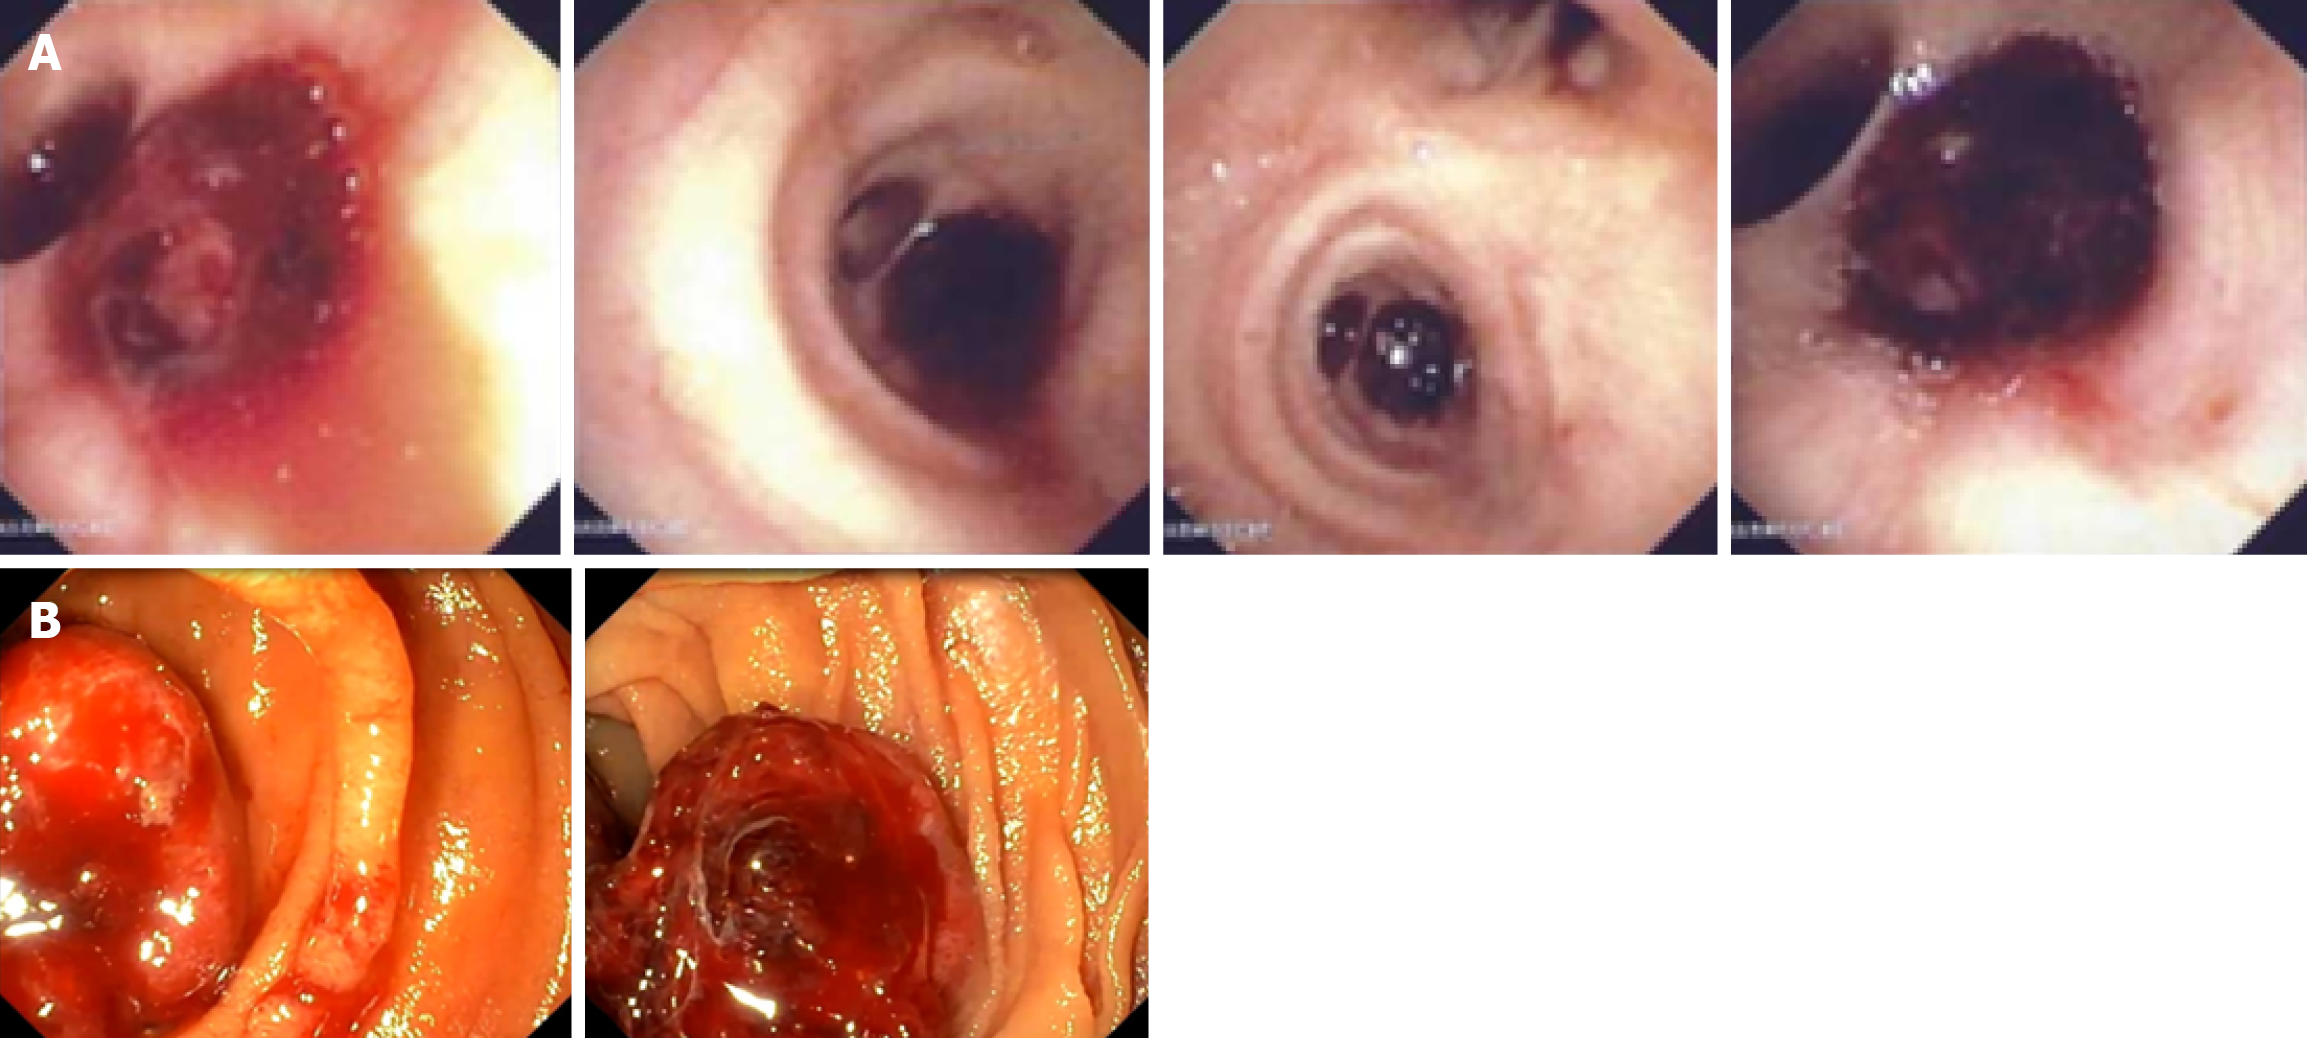

Figure 1 Video capsule endoscopy images.

A: Minor bleeding at the level of the esophagus; B: Multiple blood clots in the proximal jejunum.